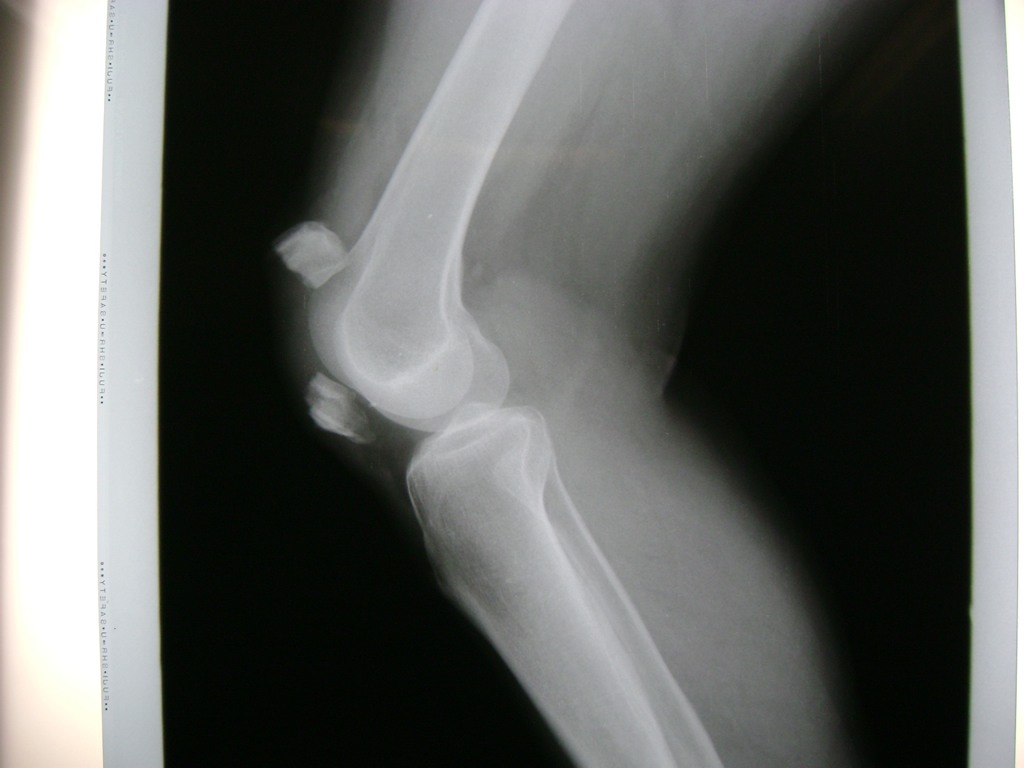

Cirugías de Calcaneo - Rodilla

La artroscopia de rodilla es un cirugía en el cual la estructura interna de la articulación es examinada ya sea para realizar un diagnostico o para realizar un tratamiento, este procedimiento se realiza utilizando un instrumento parecido a un pequeño tubo llamado artroscopio.